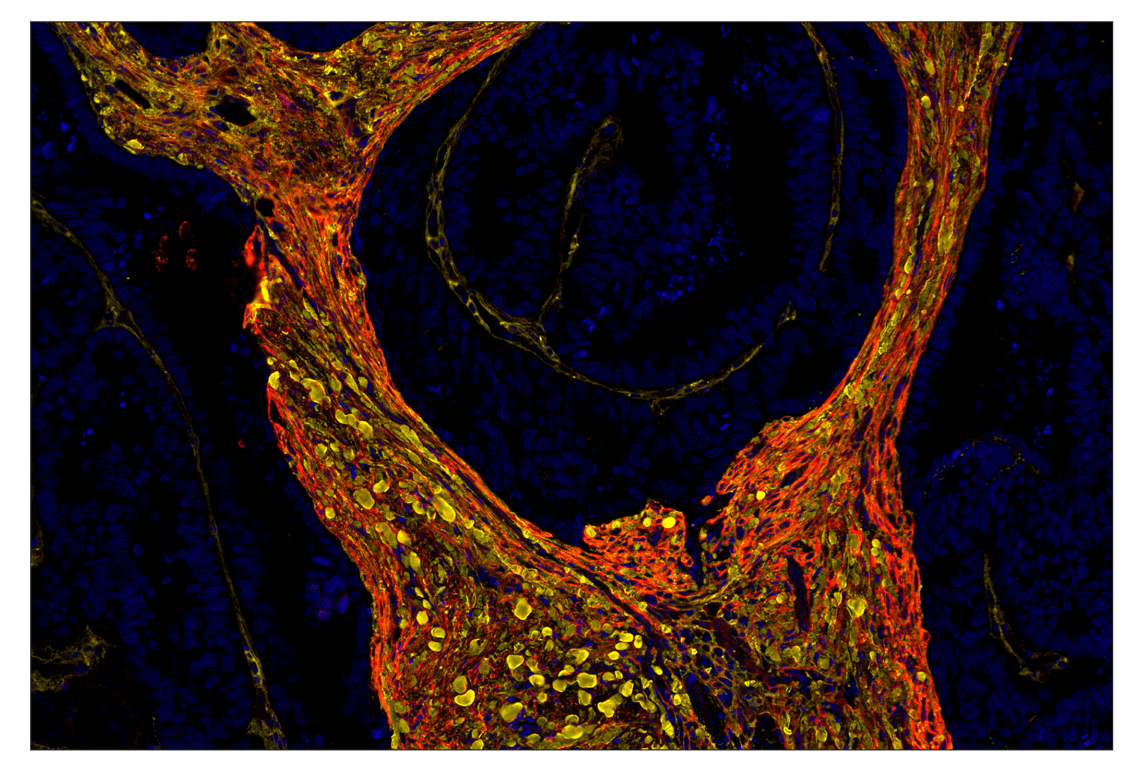

COL1A1 (E8F4L) & CO-0106-647 SignalStar™ Oligo-Antibody Pair #87785

SignalStar Oligo-Antibody Pairs are compatible with the SignalStar Multiplex IHC Buffer Kits for use in fluorescent multiplex imaging experiments. This product includes the oligo-conjugated antibodies and complementary oligos required for labeling your target protein on up to 10 slides. SignalStar Multiplex IHC Buffer Kits are required to amplify and image the target signal. Multiple oligo-antibody pairs can be conveniently combined into a multiplex panel using the SignalStar Multiplex IHC Panel Builder. SignalStar Multiplex IHC Kits & Reagents are not compatible with all of Cell Signaling Technology® products and protocols that are recommended for use in immunohistochemical assays.